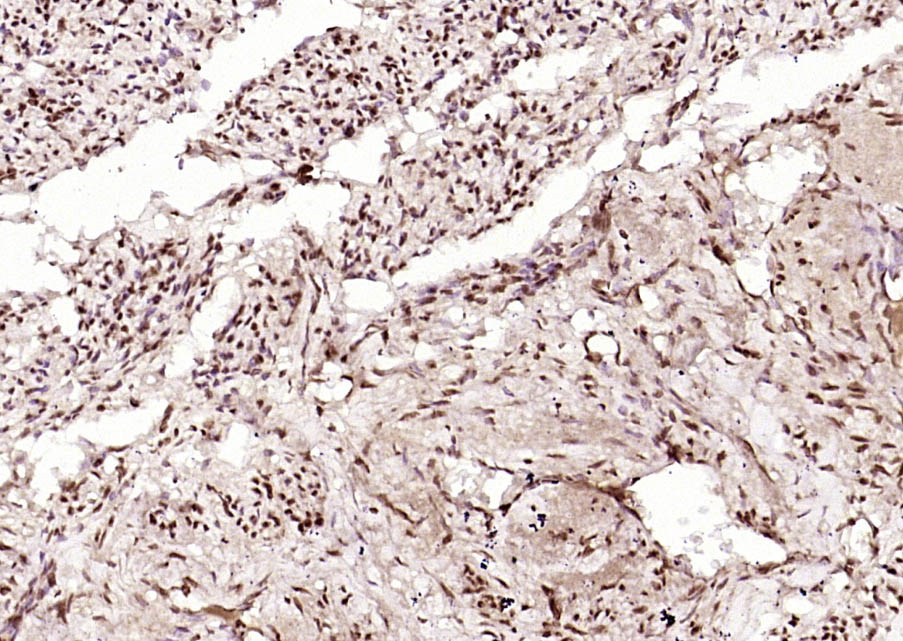

Paraformaldehyde-fixed, paraffin embedded (Human uterus); Antigen retrieval by boiling in sodium citrate buffer (pH6.0) for 15min; Block endogenous peroxidase by 3% hydrogen peroxide for 20 minutes; Blocking buffer (normal goat serum) at 37°C for 30min; Antibody incubation with (INTS3) Polyclonal Antibody, Unconjugated (bs-9766R) at 1:200 overnight at 4°C, followed by operating according to SP Kit(Rabbit) (sp-0023) instructionsand DAB staining.